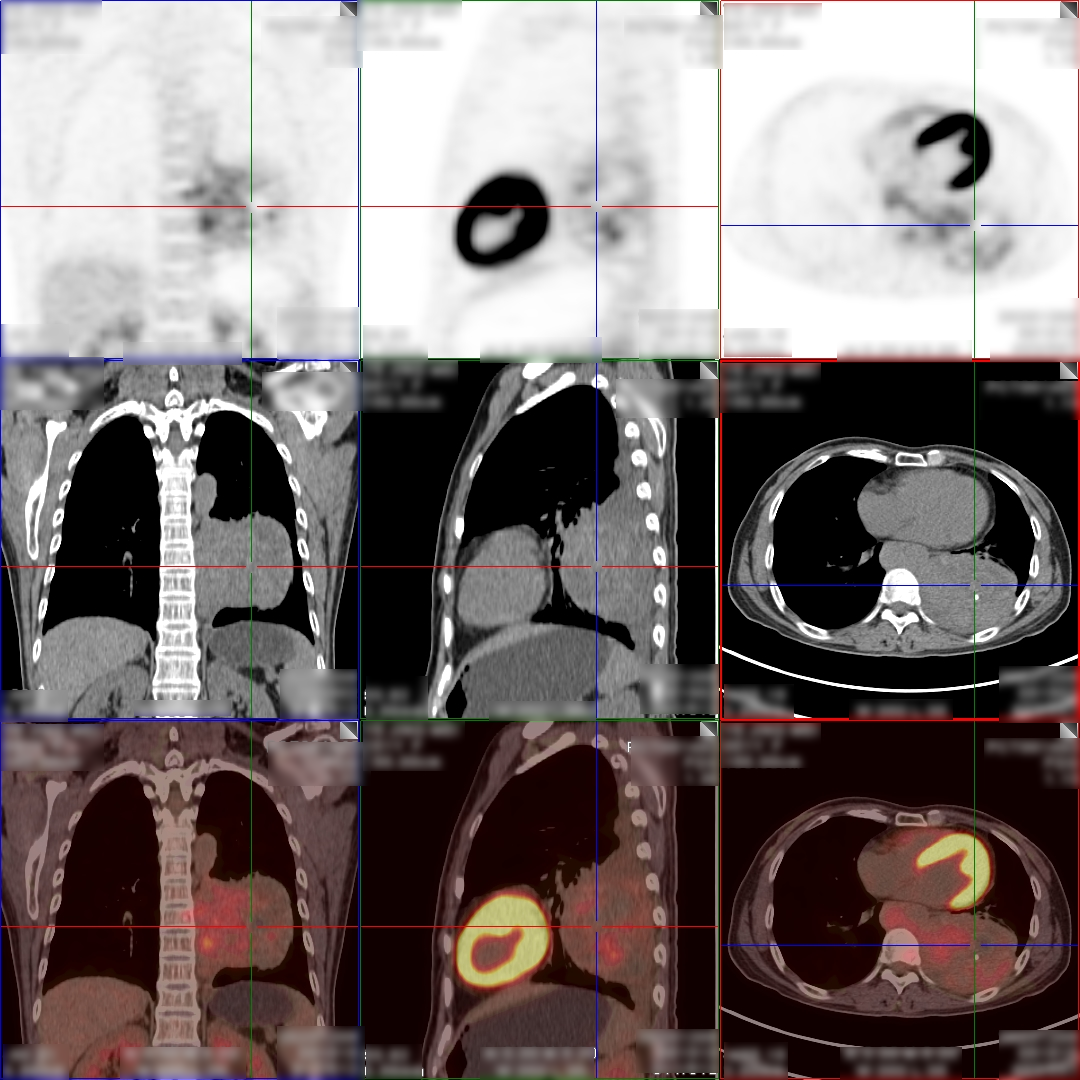

病史:女,51岁,左侧胸腔肿物约3-4年,干咳伴左侧胸痛1个月余,自服药物不能缓解。2023.12.6 CT 显示左侧胸腔及纵隔内肿块,考虑肿瘤性病变,胸膜来源低度恶性肿瘤(胸膜间皮瘤)可能。无其他病史,进食可,二便可,今年以来有体重减轻,为鉴别病灶良恶性申请PET/CT检查。

PET/CT检查所见

PET/CT诊断意见:

1、左侧胸腔内混杂密度肿块,实性组织代谢轻中度增高,考虑间叶组织来源低度恶性肿瘤,病灶内部分组织坏死,与左侧胸膜粘连并向纵隔内生长;

2、纵隔(1L、2L、3A、6、8R 组)及左侧锁骨上窝多发淋巴结转移灶;

3、胸 8 椎体左份结节状高代谢病灶,考虑骨转移灶。

PET/CT活检病理:恶性畸胎瘤